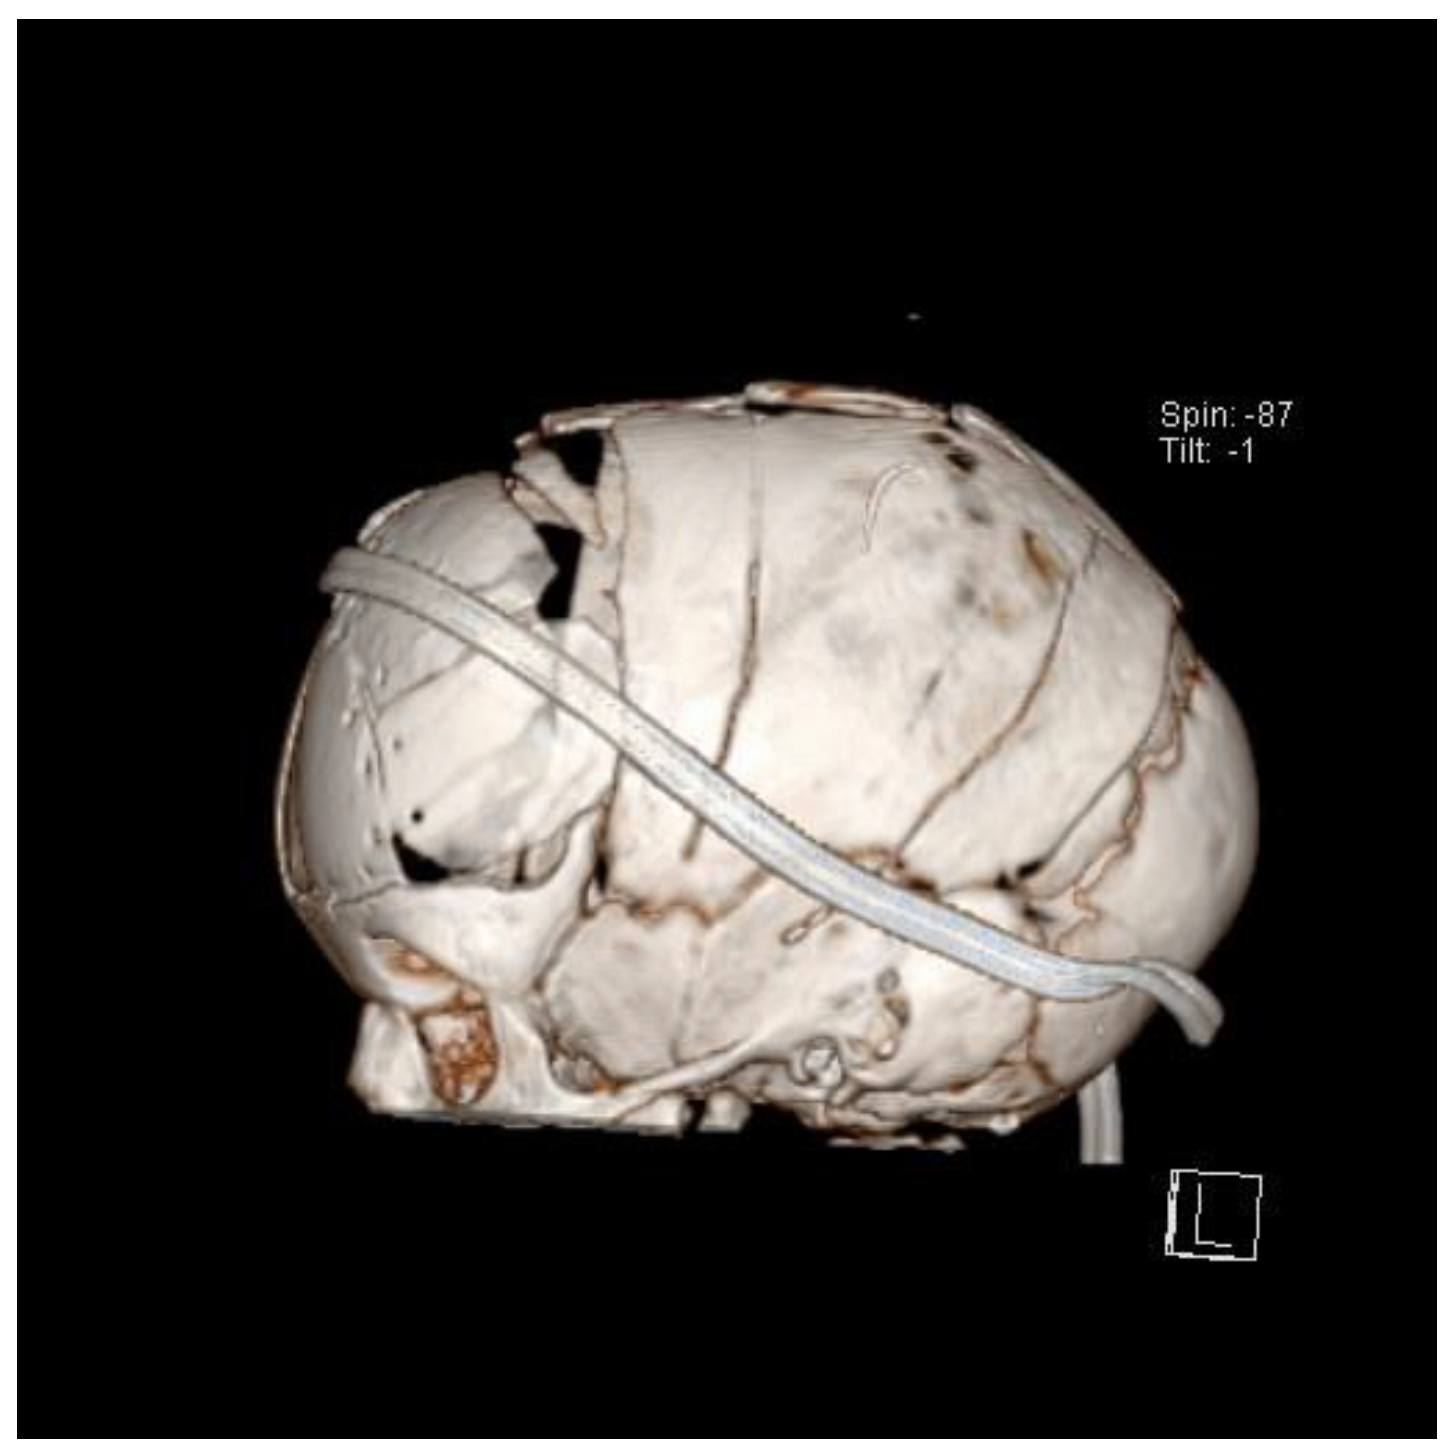

8. Surgical Techniques